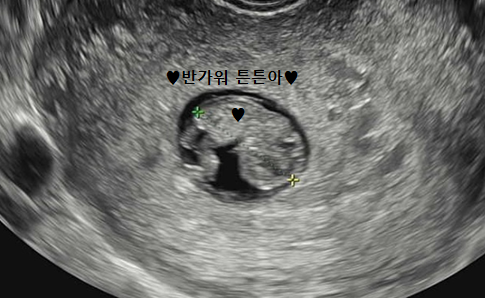

저는 아기 천사를 정말 정말 만나고 싶어서 체력과 영양제 관리를 가장 먼저 시작했어요!

건강을 위해 일주일에 최소 두 번 정도는 헬스장에 가서 러닝과 근력 운동을 하며 기초 체력을 끌어올리려고 목표를 잡았고, 운동을 하지 못한 날에는 근처 공원에서 산책하며 걸었어요.

그리고 선물 받은 비타민D와 활성엽산400이 있어서 영양제를 꾸준히 챙겨 먹던 어느 날! 선물처럼 찾아 온 우리 튼튼이♥

건강하게 만날 수 있기를 기도하며 병원을 다니기 시작했고, 피검사를 했는데 비타민D 수치가 나오긴 했으나 임산부에게 부족한 수치라는 결과를 받게 되었어요ㅠㅠ 그래서 튼튼이와 아기집 성장이 더디다는 검진 결과가 나왔던 걸까요..?

당장 제가 원래 먹던 프리솔라 비타민D 2000과 활성엽산 800으로 주문하고 먹기 시작했고, 꾸준히 빼먹지 않고 먹으려고 노력하며 헬스는 중단하고 산책하며 걷기에 집중했어요.

그 결과 한달 후 검사한 결과에서 비타민D가 정상수치로 나왔고, 튼튼이는 천천히 자랐지만 건강하게 잘자라줘서 난임병원을 졸업할 수 있었습니다!!! 튼튼아 튼튼하게만 자라서 우리 건강한 모습으로 만나자^^